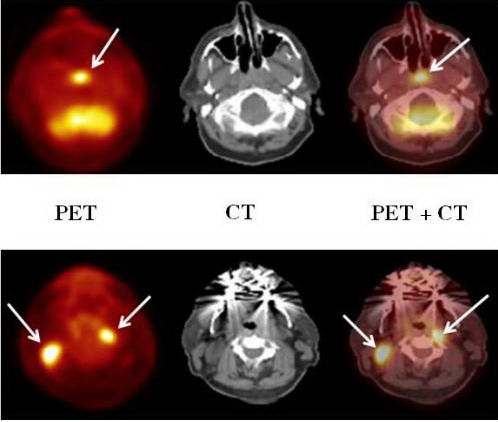

4.2. Ghi hình với PET/CT

Ghi hình với máy PET/CT là một trong những kỹ thuật ghi

hình hiện đại nhất hiện nay. Với cách kết hợp này chúng ta sẽ tận dụng những ưu

điểm của CT và của PET.

Kết hợp máy PET với CT – Scanner tức là ghép 2 loại đầu dò

trên một máy và dùng chung hệ thống ghi nhận lưu giữ số liệu và các kỹ thuật

của máy tính.

Do bệnh nhân đồng thời vừa được chụp CT vừa được chụp PET,

nên hệ thống này cho phép ghép chồng hình ảnh của CT và xạ hình (PET) lên nhau.

Sự phối hợp hình ảnh trên đã giúp chẩn đoán bệnh ở giai đoạn

rất sớm, chính xác, tăng độ nhạy, độ đặc hiệu của kỹ thuật PET/CT nhờ có được

đồng thời hình ảnh cấu trúc gỉai phẫu của CT và hình ảnh chức năng chuyển hoá

của PET.

Như vậy ghi hình với PET/CT sẽ cho hình ảnh kết hợp của:

CT: với hình ảnh cấu trúc gỉai phẫu rõ nét, và đóng vai

trò như một khuôn mẫu định dạng các tổ chức giải phẫu chính xác ở vị trị cần

nghiên cứu và cần chẩn đoán.

PET: với hình ảnh chức năng, các tổn thương được phát

hiện rất sớm với độ nhạy cao. PET có độ nhạy và độ đặc hiệu cao

trong phát hiện tổn thương, đặc biệt trong ung thư.

FDG-PET